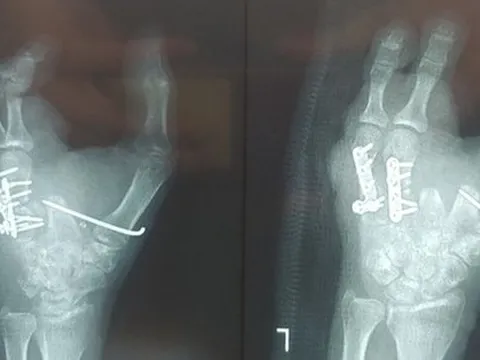

Lắp ngón chân thành ngón tay cho bệnh nhân

Bệnh nhân nữ bị máy xay thịt cuốn nát bàn tay trái khiến ngón 2, 3, 4, 5 không thể phục hồi. Các bác sĩ đã phẫu thuật đưa ngón chân thành ngón tay cho bệnh nhân